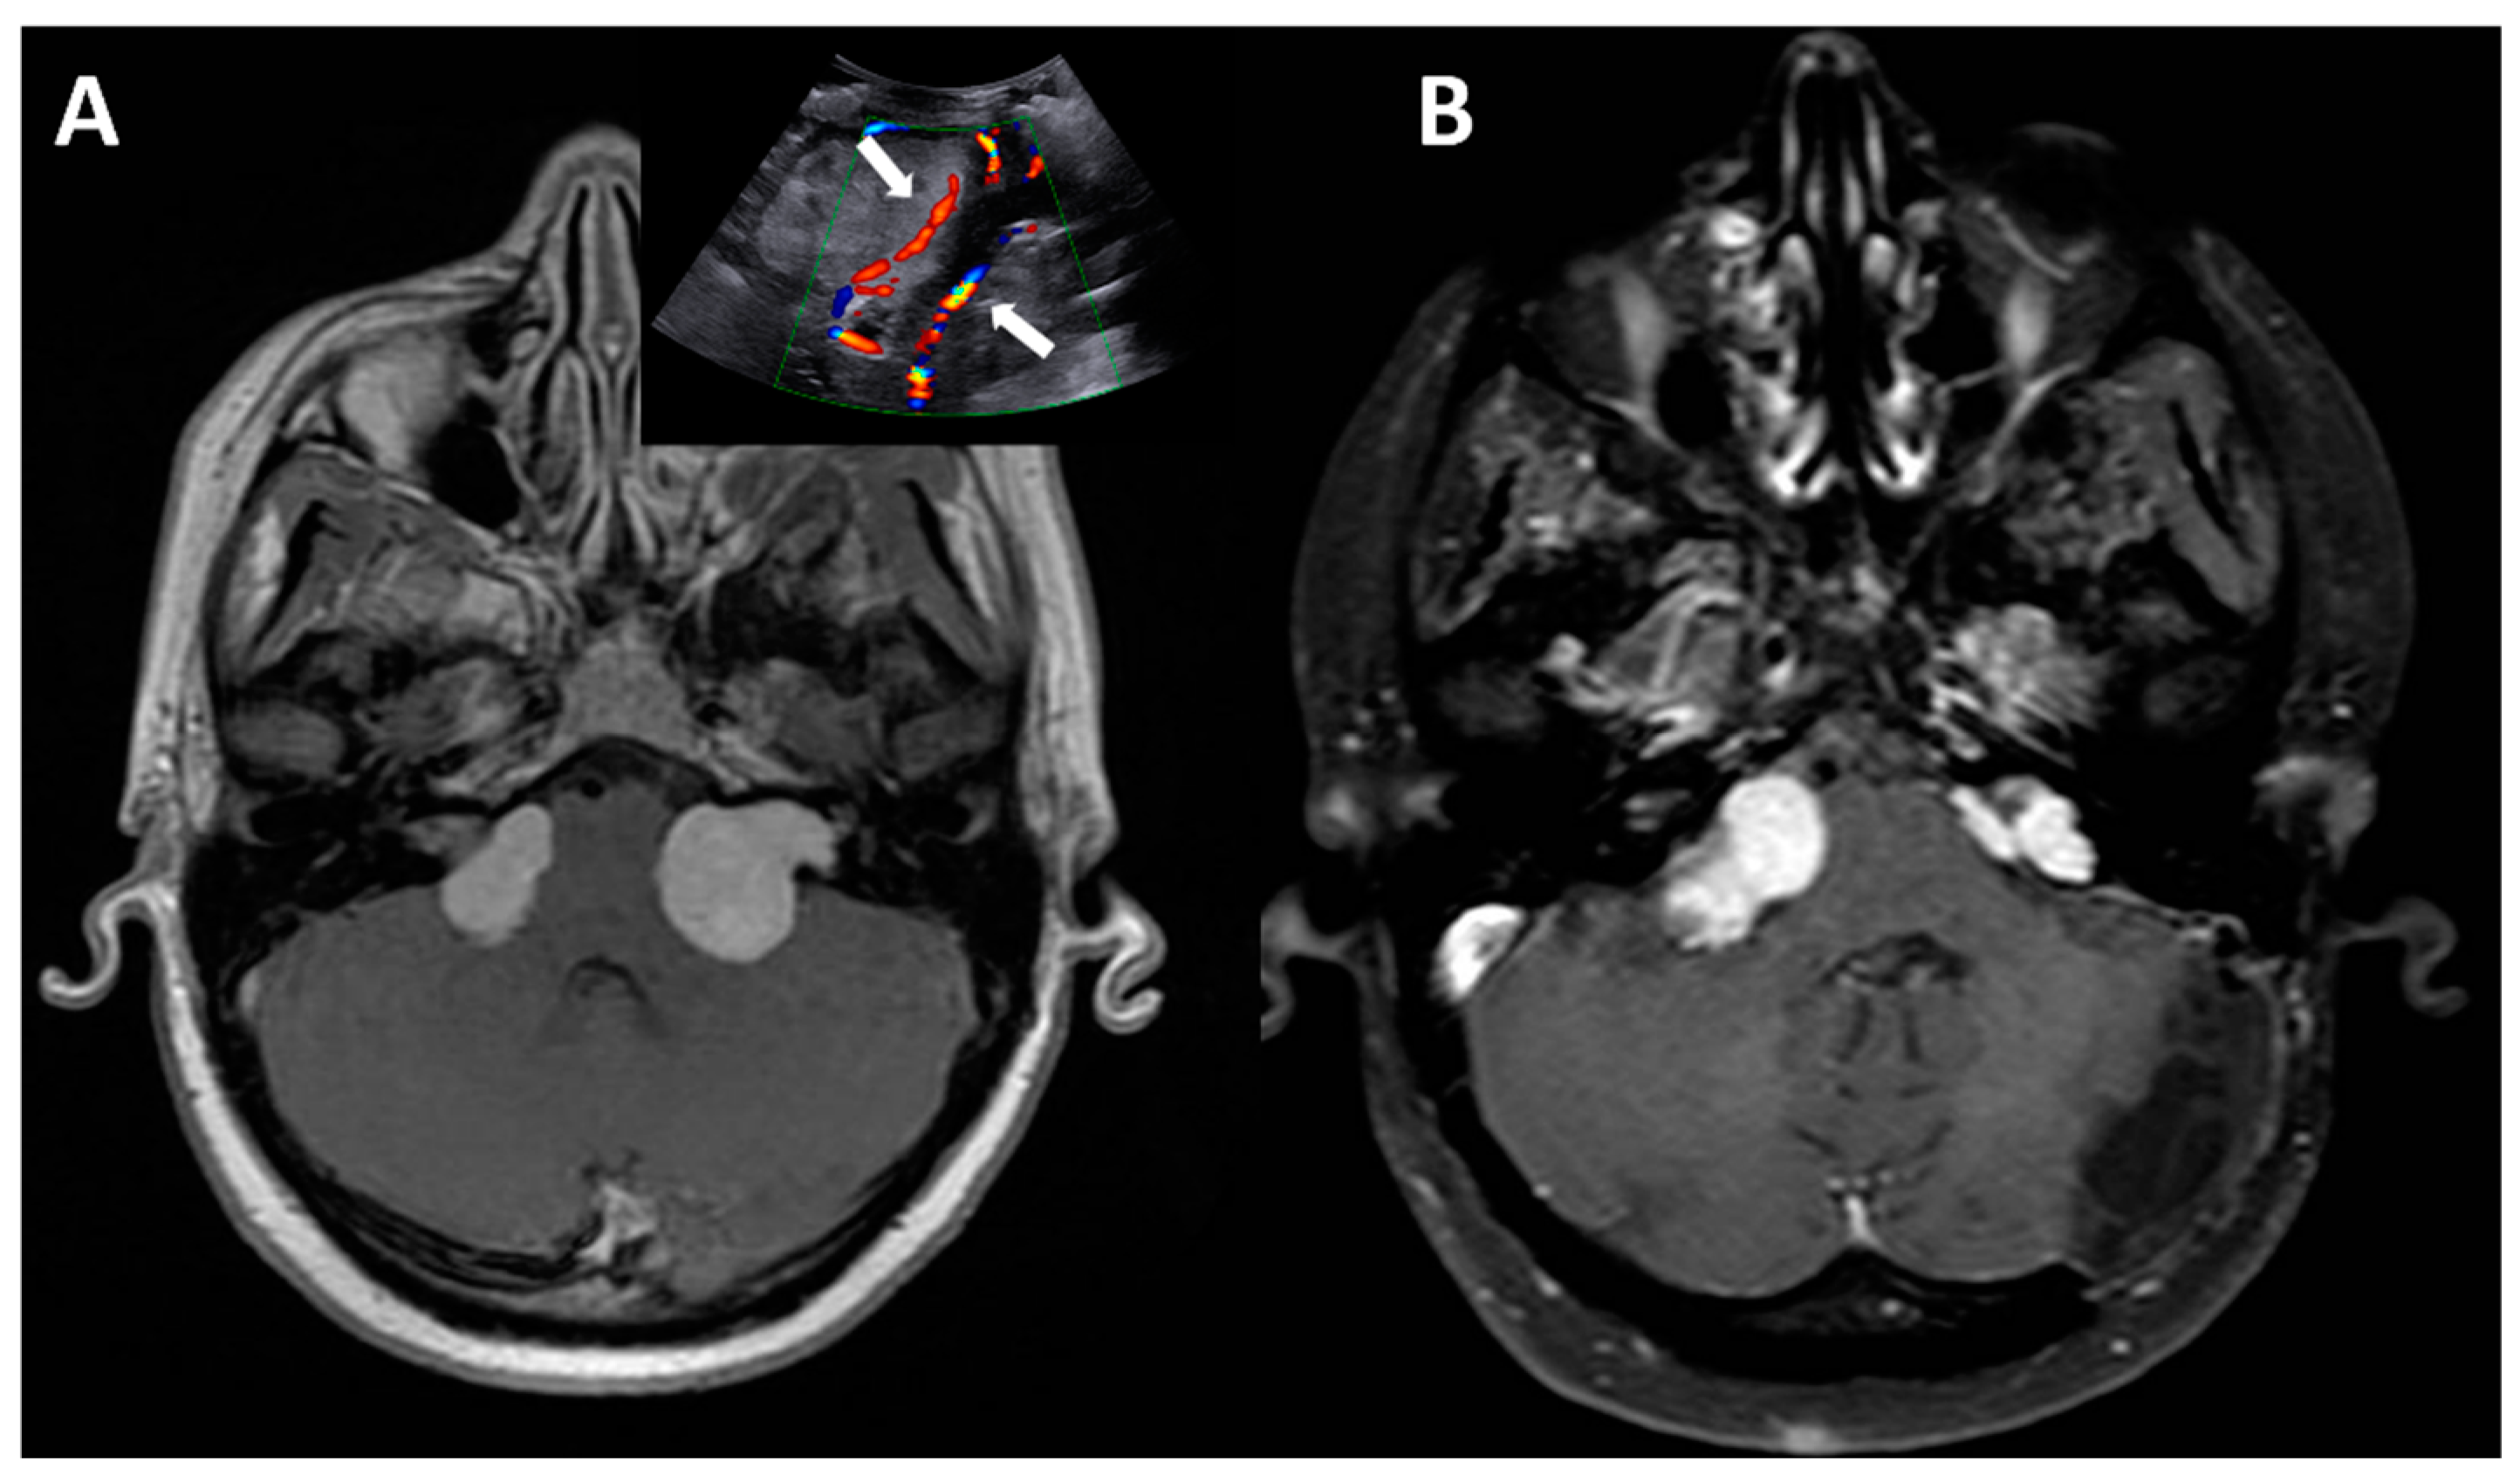

Figure 2. T2 axial MRI showing the preoperative (A) and postoperative picture (B) of a low grade glioma (9-year-old girl) arising from the brainstem and extending into the right CPA. IOUS clearly show the tumor (C) and its GTR (D).